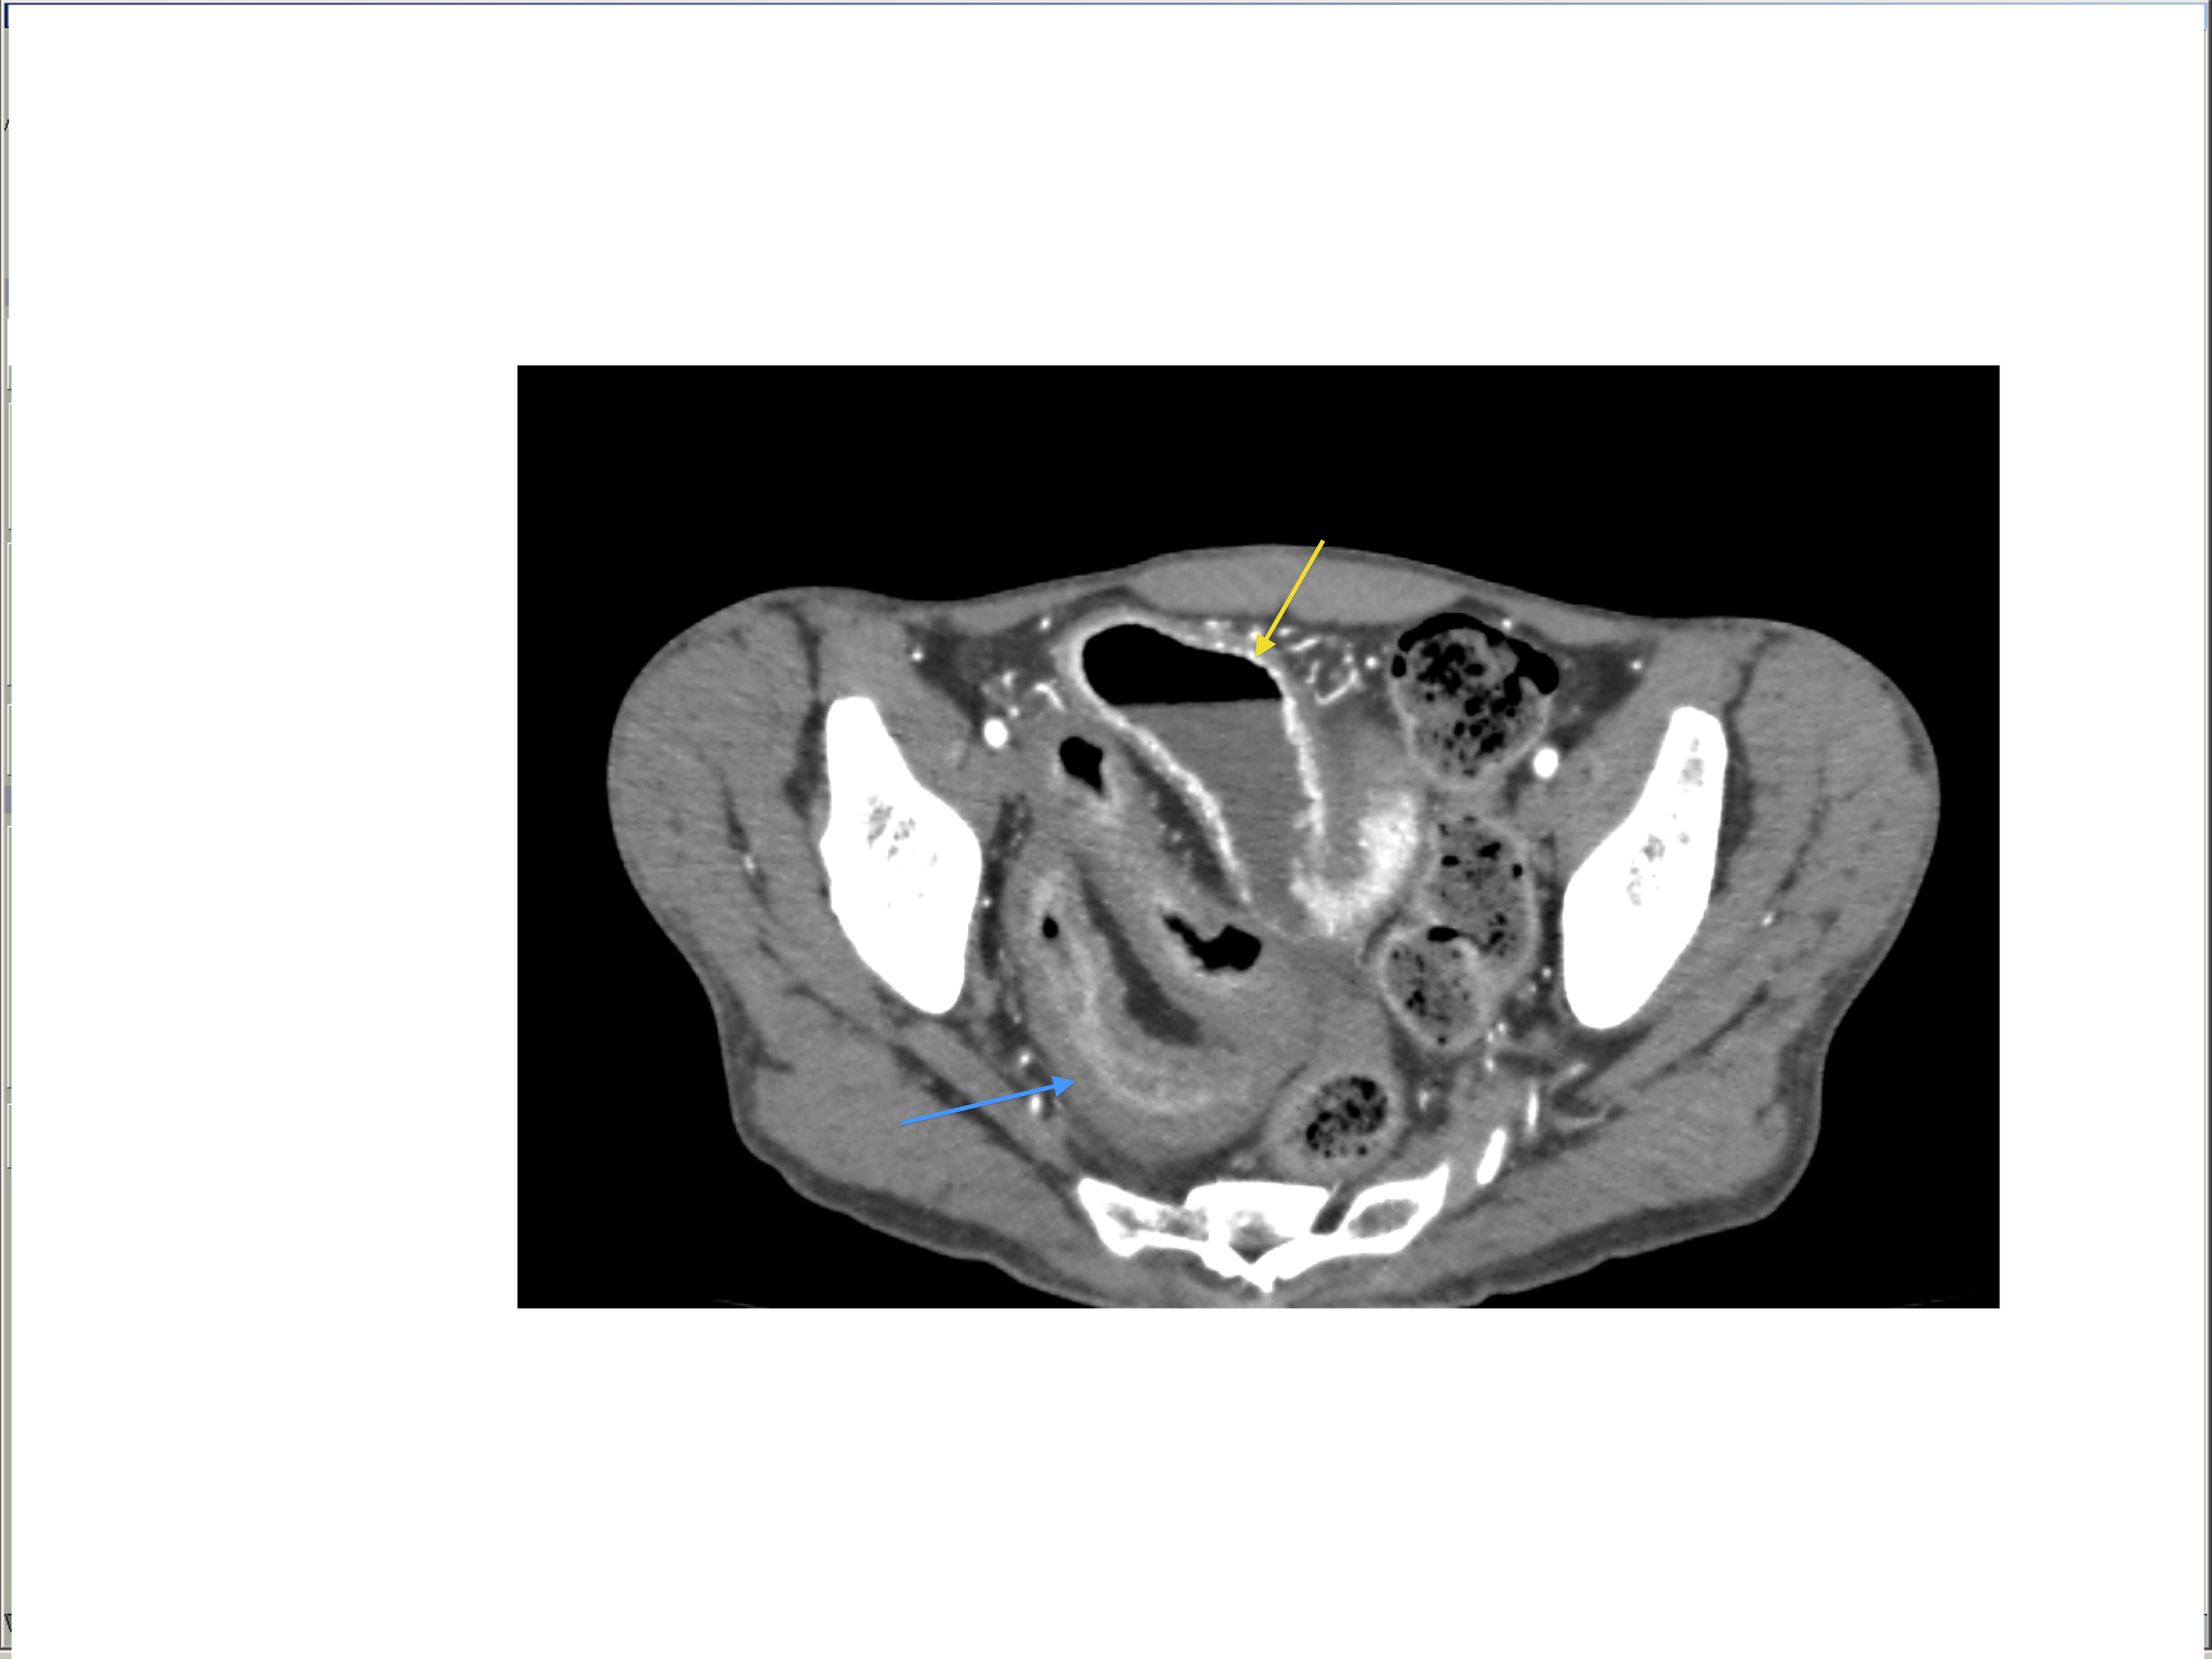

Small bowel obstruction is a common clinical presentation that presents a diagnostic conundrum. Over the last 2 decades, there has been a paradigm shift in the radiological investigation of small bowel obstruction (SBO) and in the indication for and timing of surgical intervention. Cross sectional imaging (predominantly computed tomography) has largely replaced the widespread use of radiographic small bowel follow-through studies as the imaging modality of choice for SBO. This article illustrates the current imaging modalities available for diagnosis of small bowel obstruction. (Full text available online at www.medpharm.tandfonline.com/ojfp) S Afr Fam Pract 2015; DOI: /10.1080/20786190.2014.977052